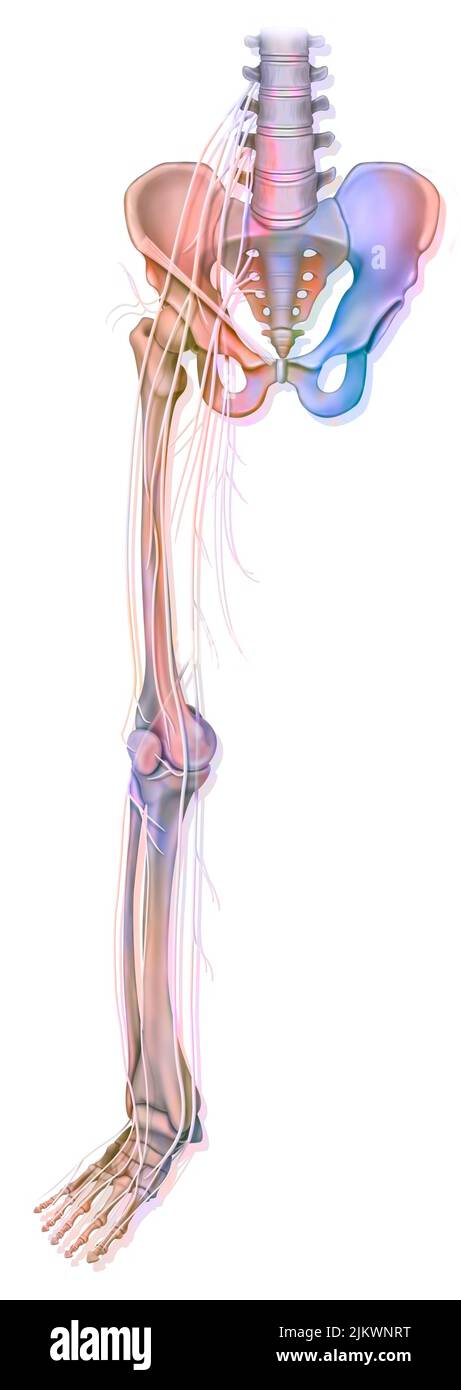

Anatomie des nerfs du membre inférieur (jambe). Banque D'Imageshttps://www.alamyimages.fr/image-license-details/?v=1https://www.alamyimages.fr/anatomie-des-nerfs-du-membre-inferieur-jambe-image476924332.html

Anatomie des nerfs du membre inférieur (jambe). Banque D'Imageshttps://www.alamyimages.fr/image-license-details/?v=1https://www.alamyimages.fr/anatomie-des-nerfs-du-membre-inferieur-jambe-image476924332.htmlRF2JKWNRT–Anatomie des nerfs du membre inférieur (jambe).